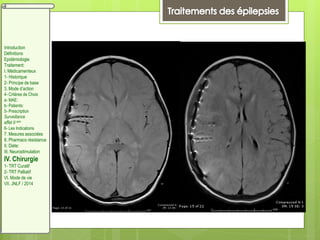

Figure 1.

Le potentiel d'action est le mode de transmission de l'information le long de l'axone puis de neurone en neurone

par la transmission synaptique. Il est généré par ouverture successive de canaux voltage-dépendants (Na+ puis

K+). La transmission synaptique se fait par le relargage de neurotransmetteurs dans la fente synaptique, qui vont

se fixer sur les récepteur du neurone post synaptique entraînant une (dépolarisation ou une repolarisation) selon

qu'il s'agisse de la voie excitatrice ou inhibitrice.

GABA : acide gamma-aminobutyrique ; AMPA : alpha-amino-3-hydroxy-5-méthylisoazol-4-propionate ; NMDA : acide N-

méthyl-D-aspartique.